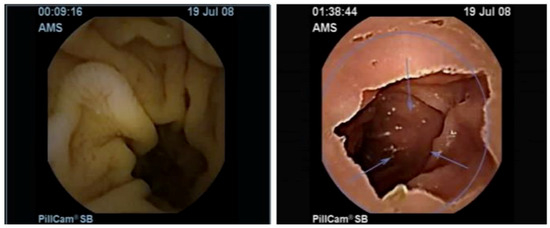

2.1. Wireless Capsule Endoscopy

5.1. Dataset